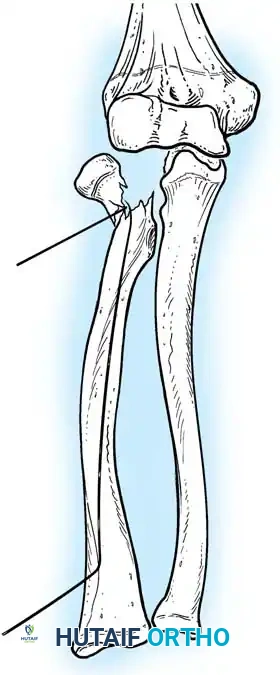

Fig. 33-37 Overcorrection with medial convexity for lateral dislocation.